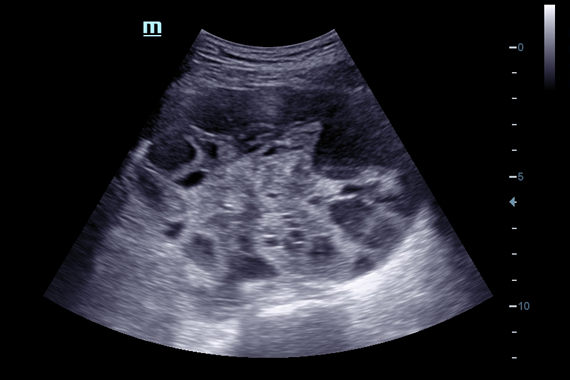

Система ультразвукового исследования Mindray DC-60 EXP X-INSIGHT является новейшей разработкой для проведения комплексных обследований на высшем уровне. Она обеспечивает решение самых сложных задач в таких областях, как кардиология, акушерство и гинекология, сосудистые заболевания, педиатрия и многие другие.

DC-60 EXP X-INSIGHT - это современный стационарный УЗИ-аппарат с функцией сенсорного управления и очищенной гармонической визуализацией, обеспечивающей лучшее контрастное разрешение и технологию 4D-визуализации. Он оснащен 21,5-дюймовым монитором, который может поворачиваться на 180 градусов, что удовлетворяет потребности врачей в качественной ультразвуковой диагностике.

Одним из ключевых преимуществ DC-60 EXP X-INSIGHT является технология формирования УЗ-луча. Она дополняет основной луч параллельно эхо-сигналами, что приводит к получению более мощного сигнала и изображений высокого качества с помощью систем iLive, iPage, Smart OB, Smart NT.